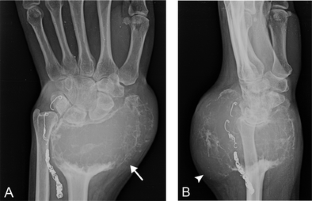

Fig. 2